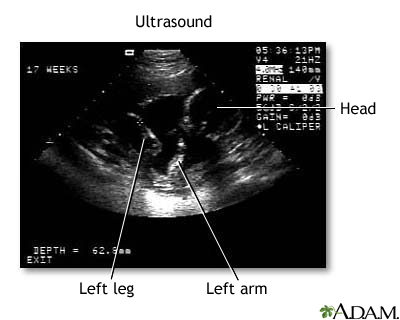

This is a normal fetal ultrasound performed at 17 weeks gestation. The development of the brain and nervous system begins early in fetal development. During an ultrasound, the technician usually looks for the presence of brain ventricles. Ventricles are spaces in the brain that are filled with fluid. In this early ultrasound, the ventricles can be seen as light lines extending through the skull, seen in the upper right side of the image.